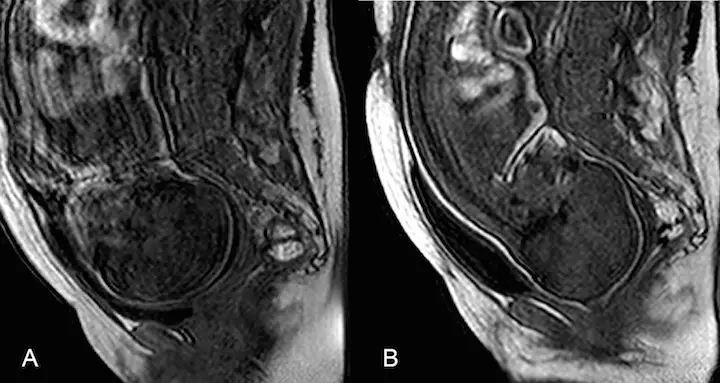

Crédits Photo : PLOS ONE, Ami et al. 2019 - Images obtenue par IRM avant et pendant l’accouchement. Photo A : La tête du fœtus n’est pas modelée. Le bébé n’est pas encore passé au niveau du bassin de la mère. Photo B : La tête du fœtus passe par la cavité pelvienne, pendant le deuxième stade de l’accouchement. Elle prend une forme conique typique en "pain de sucre".